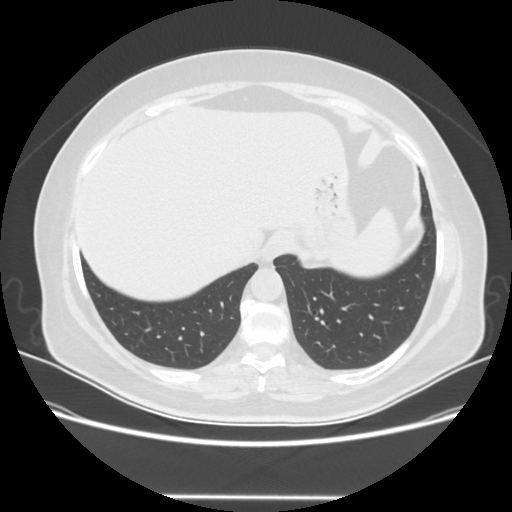

Targeted Slice 70 - Lung Window Analysis (Generated vs Real Venous)

0.782

Lung SSIM

70.6

Lung RMSE

32.3

Lung MAE

Average Lung Window Metrics Across All Slices (25 slices) - Generated vs Real Venous

0.771

Lung SSIM (Avg)

72.3

Lung RMSE (Avg)

34.1

Lung MAE (Avg)

Original VENOUS CT scan

No window - Raw intensity values

Lung window (WL -600, WW 1500 β†’ Low βˆ’1350, High +150)